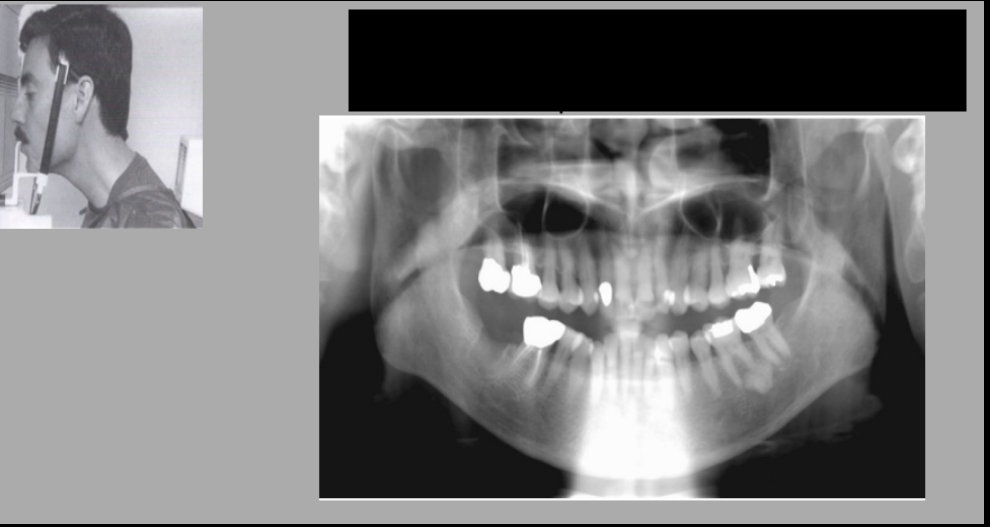

Name the errors

Palatoglossal space

earring ghost image

What errors do we see?

A. Chin too high and forward

B. Pt. is laughing

C. Chin too low and head too far back

D. Chin too low and head is too far forward